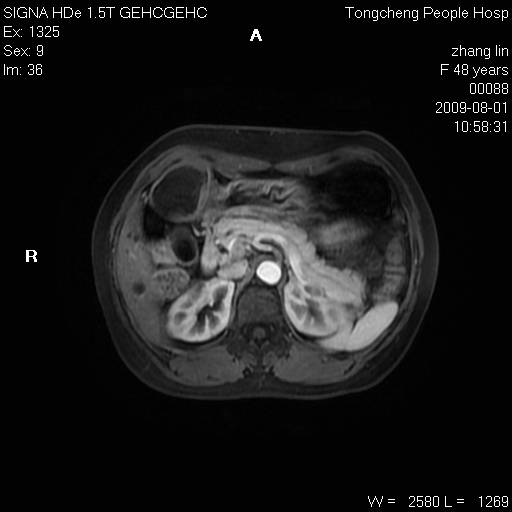

女,48岁。健康体检,彩超发现右肾占位性病变。平素健康。

临床诊断:右肾占位性病变,性质待定(囊肿?肿瘤?)。

上中腹部mr平扫+增强扫描,图像如下:

右肾上极见一类圆形病灶,t1wi呈等信号t2wi呈等高混杂信号,三期增强无强化,边界清---考虑囊肿出血。

同反相位均表现为等信号,病变无强化,考虑含蛋白的囊肿可能,弥散加权相或许有些帮助,